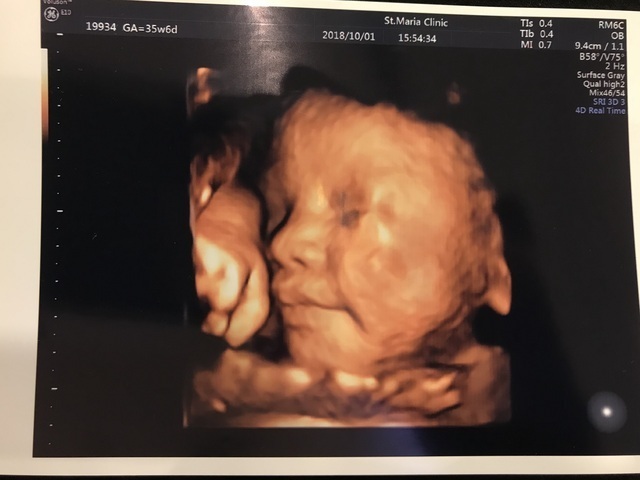

35週6日(35w6d・女の子)|norienorie さん(32歳)

エコー写真撮影時のエピソード:

びっくりするくらいクッキリとした顔で鼻筋も通っていていました。本当にこんな感じなのかな?とびっくりしましたが、主人がとてもハッキリとした顔をしていて、産まれた後我が子を見て本当にエコー通りだと思いました。

私は産まれるまでにおい悪阻、子宮筋腫、15週あたりで出血など色々悩まされていましたが、いつもエコー写真を見るたびに我が子に励まされて乗り越えることができました。

色んなものを抱えて臨んだ妊娠でしたが、無事に五体満足に産まれてきてくれた我が子に本当に感謝しています。

エコー写真は絵本のような日記にまとめて宝物となっています。

その絵本は我が子が大人になってお嫁に行くときにプレゼントしようと決めています。